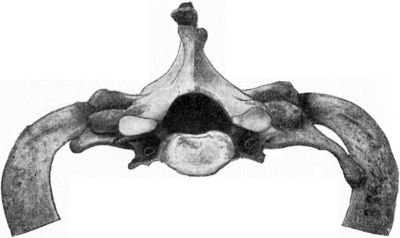

209.Fracture of Odontoid Process of Axis Vertebra429